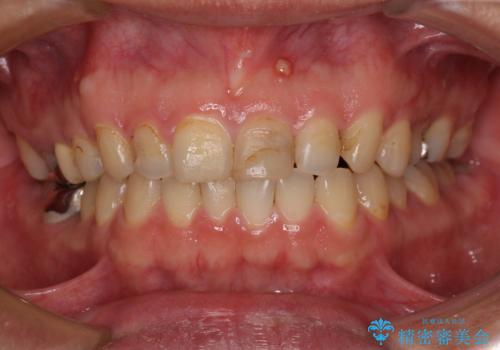

- 前歯の色を気にして来院された患者様です。

むし歯で神経が取り除かれており、歯の変色と充填材の変色などにより、つぎはぎのような前歯となっていました。

膿の出口も認められたため、まずは根管治療を実施し、オールセラミッククラウンにて補綴治療を行うこととしました。